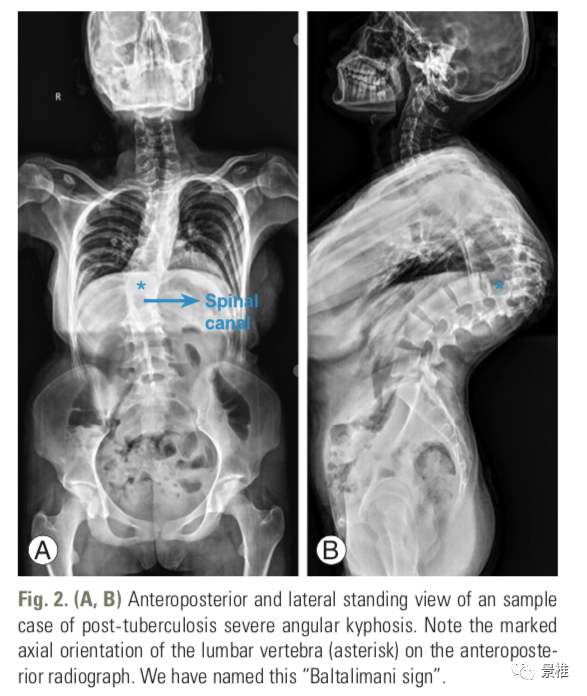

土耳其伊斯坦布尔xxx Baltalimani骨病医院的学者发现了一个脊柱严重角状后凸(≥90°)正位X线片的影像学征象,将其命名为 Baltalimani征

土耳其伊斯坦布尔xxx Baltalimani骨病医院的学者发现了一个脊柱严重角状后凸(≥90°)正位X线片的影像学征象,将其命名为 Baltalimani征。

Baltalimani征阳性:脊柱严重角状后凸(SAK)的顶椎相邻椎体处于垂直翻转状态。在正位x线片上可以观察到椎体轮廓呈轴位观。

Baltalimani征阳性的正侧位X片示例。这种严重成角压迫使得脊髓损伤发生几率比阴性征象增加了61.9%